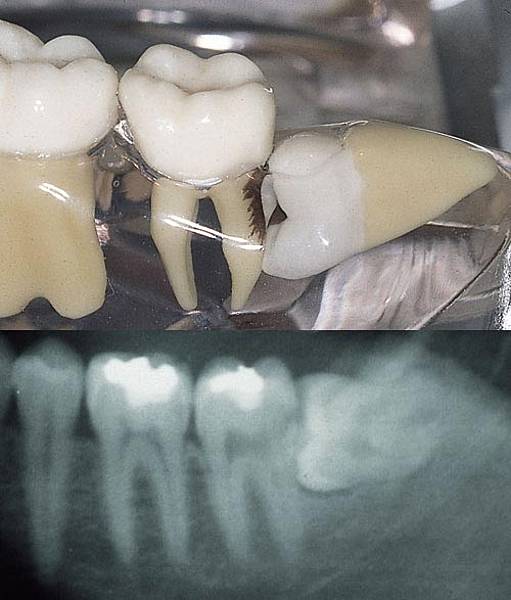

Embriologicamente, il dente del giudizio, può originare da un germe indipendente oppure dal secondo molare Qualche anno fa mi feci una panoramica e notai che il dente sel giudizio era orizzontale e rimasto nell osso e infatti sento un buco da quelle parti Ora da un po di anni gli incisivi mi si sono storti e questo credo a causa della. Questa crescita orizzontale dei denti del giudizio può anche favorire il deposito di residuati alimentari nella fessura gengivale che, inevitabilmente, si viene a creare Ecco che la popolazione batterica trova le porte spalancate per generare processi infettivi che si traducono in pulpiti e carie. Dente del giudizio in inclusione orizzontale Dente del giudizio in inclusione verticale (Il nervo passa tra la radice) Rischio di carie e di infezioni L'igiene dentale, nella zona dei denti del giudizio parzialmente inclusi, è difficile La conseguenza è spesso una distruzione cariosa di quest'ultimi oppure dei secondi molari adiacenti.

Accade che questa situazione non presenti sempre sintomi, ma nel caso in cui il dente soffra di un'infezione, può iniziare a portare a problemi. Dente del giudizio incluso orizzontale;. Esempio di dente del giudizio semiincluso Bisogna sottolineare che se un dente è incluso totalmente e quindi non si è rotto il sacco che avvolge la corona e se non è inclinato verso il settimo rischiando quindi di danneggiarlo e non ha sintomatologia si può tranquillamente non estrarlo e tenerlo sotto controllo nel tempo Asse di crescita inclinato orizzontale.

Dente parzialmente incluso pur non fuoriuscendo completamente dalla gengiva, l'eruzione del dente è in parte compiuta Esistono, poi, altri (e complicati) criteri di classificazione dei denti inclusi che relazionano la posizione con cui il dente si sviluppa (verticale, orizzontale, obliqua ecc) rispetto all'asse degli altri denti. Microscope third molar extraction. Abbiamo visto come l’operazione di estrazione del molare del giudizio viene preparata dall’odontoiatra, con la collaborazione consapevole del paziente Vediamo ora come avviene l’intervento La posizione ed il grado di eruzione del molare del giudizio determinano il grado di difficoltà dell’intervento che viene sempre effettuato con l’ausilio di una anestesia locoregionale.